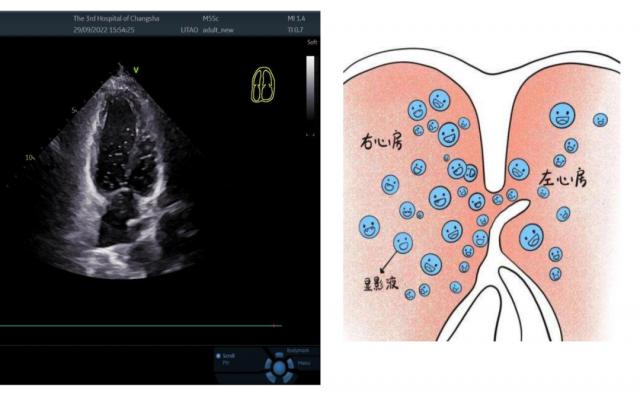

超声波诊断科主治医生李建春在检查心脏时,特别仔细地看了看卵圆孔的位置。隐约发现房间间隔中间有斜裂缝样回声失落,疑似卵圆孔未闭;进一步右心造影验证了医生的判断。黎女性被诊断为卵圆孔未闭。(PFO-RLS III 级)。

李涛说,临床上主要通过超声心动图和声学造影来诊断卵圆孔未闭症,包括胸部超声心动图。(TTE)经胸超声心动图声学造影(cTTE)、通过食管超声心动图(TEE)和通过食管超声心动图声学造影(cTEE)、比较增强经颅多普勒超声学造影。(cTCD)等技术。